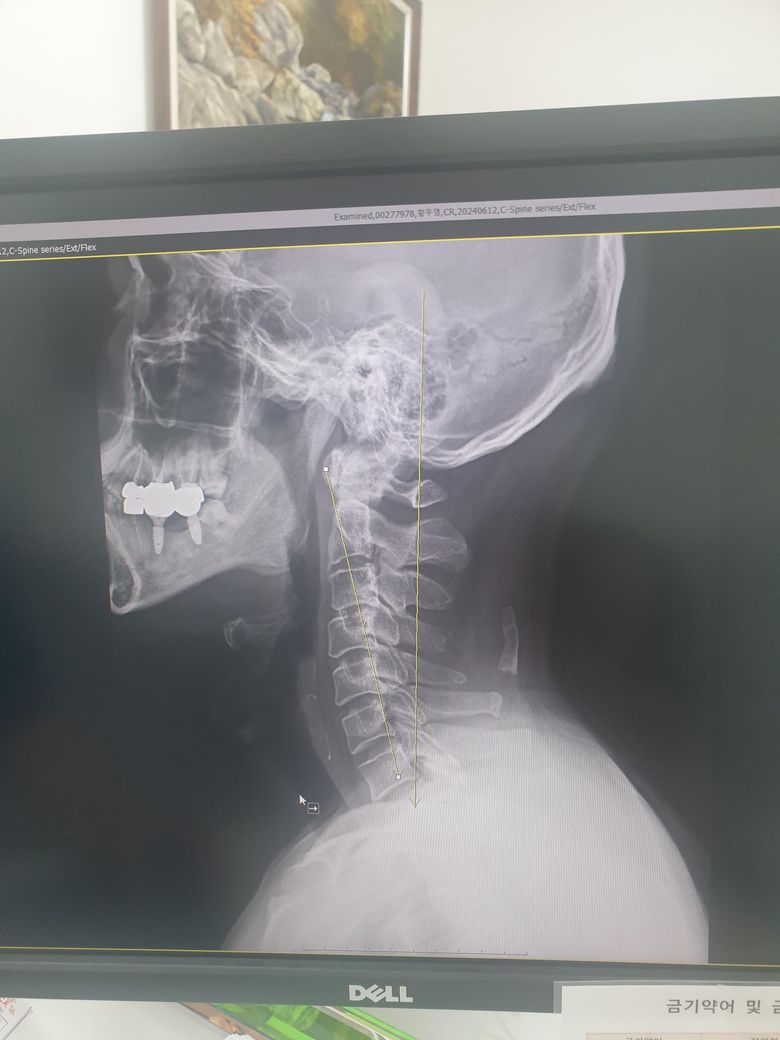

목 x_ray 한번 봐 주세요.궁금합니다

요즘 목과 등에 담이 자주걸려서 목주위를 만지다가 경추4번5번 지점에 뼈인지는 모르나 볼록 퇴어나와 있어 병원에서 X_Ray결과 석회뼈라고 하고 지장이 없다고 하고

담이 자주 걸리는것은 거북목이라 승모근에 항상 스트레스가 있어서 그렇다고 하는데 제대로 된 진단인지 모르겠어요.다른 병원에 한번더 가봐야 하나요.참고로 신경외과에서 진료받았어요.이상하게 손가락처럼 생긴 뼈같은게 제거안해도 되는지 아님 이게 움직이면서 신경쪽에라도 건드려서 문제가 되지 않는지 궁금합니다.

엑세레이에서 보이는 저런 부골 (accessory bone)이 굉장히 흔하게 발견됩니다.

전혀 걱정하지 않으셔도 되고 신경은 척추뼈 안에 위치하고 있기 때문에 부골의 위치와는 완전히 동떨어져있습니다.

• 현재 엑스레이에서 목티 쪽으로 손가락처럼 보이는 것은 목에 있는 인대 안의 종자골일 가능성이 높으며 이는 크게 통증을 일으키지 않는 경우가 많으므로 크게 걱정하지 않으셔도 되겠습니다.

경추에 석회화가 생긴것은 흔한 퇴행성 변화로 대부분 신경에 큰 영향을 주지 않으면 치료 없이 관찰만 합니다. 담과 승모근 통증은 거북목 자세로 인한 근육 긴장때문일 가능성이 높아 자세 교정과 근육 이완 치료가 중요해요 불안하면 정형외과나 재활의학과에서 추가 검진을 받아 확인하는 것도 추천드려요!